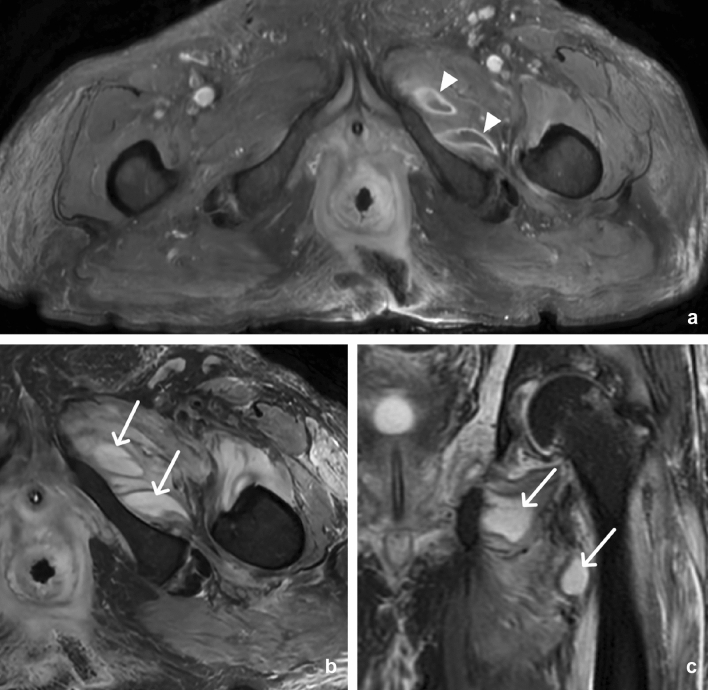

Klippel-Trenaunay-Weber syndrome

With an incidence of 1 out of 275,000 births, Klippel-Trenaunay-Weber Syndrome (KTS) is a sporadic, rare, congenital syndrome characterized by port-wine stain (nevus flammeus), vascular malformations (varicosities and hemangiomas), asymmetric appendicular bone, and soft tissue hypertrophy. Only two of the three criteria need to be present to make a diagnosis KTS. The involvement of the gastrointestinal and genitourinary systems is not uncommon. Routine CT can detect enlargement of the extremity with bone elongation and circumferential soft tissue hypertrophy, subcutaneous varicose veins, phleboliths, and capillary malformation suggesting the diagnosis (Fig. 24). MRI and MR angiography (MRA) are beneficial to evaluate vascular malformation preoperatively [50].

Fig. 24.

30-year-old male with Klippel-Trenaunay-Weber Syndrome. Axial mid-abdomen CT (a) images demonstrate enlargement of the subcutaneous tissue of the right flank (arrow) and large splenic hemangioma (arrowhead). Axial pelvic CT (b) images show mesenteric venous malformations associated with phleboliths (arrowhead) and colonic hemangiomatosis with phleboliths (arrow). Coronal posterior abdomen CT (c) images show splenic and mesenteric hemangiomas with associated calcifications (arrow). Axial upper thigh CT (d) images demonstrate gigantism of the right lower extremity with soft tissue hypertrophy and numerous subcutaneous varicose veins (arrow)